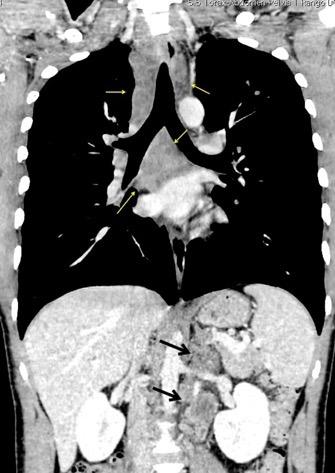

Nódulos pulmonares múltiples. (flechas verdes). Masas paratraqueales. (flechas amarillas). Dudoso ensanchamiento retrocrural (flechas negras). sigue….

Ttawfik A et al. Trans-diaphragmatic Pathologies: Anatomical Background and Spread of Disease on cross-sectional Imaging. Current Problems in Diagnostic Radiology. 2021.

T. mixto de células germinales del testículo

izquierdo Metástasis pulmonares. (flechas verdes). Ganglios paratraqueales. (flechas amarillas). Ganglios retroperitoneales (flechas negras)

Tawfik A et al. Trans-diaphragmatic Pathologies: Anatomical Background and Spread of Disease on cross-sectional Imaging. Current Problems in Diagnostic Radiology. 2021.